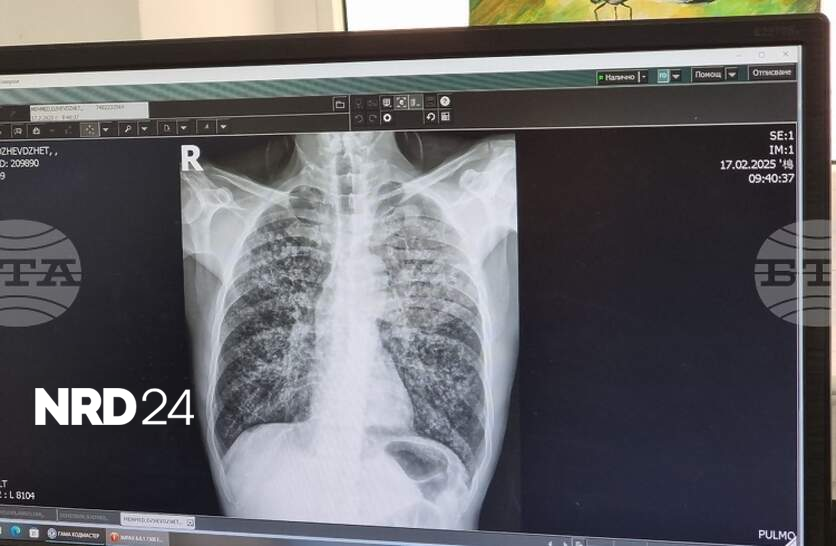

Един новооткрит случай на туберкулоза е регистриран в Ямбол по време на безплатните профилактични прегледи, организирани в периода 23 – 27 март, съобщи директорът на Регионалната здравна инспекция (РЗИ) д-р Радостина Калчева. Болестта е потвърдена при 35-годишен мъж от областния град, който е хоспитализиран в Многопрофилната болница за активно лечение (МБАЛ) „Св. Пантелеймон” в Ямбол. По повод Световния ден за борба с туберкулозата – 24 март, в областната болница се извършваха безплатни прегледи и изследвания за болестта в пневмо-фтизиатричното отделение. През скрининг са минали общо 35 души на възраст между 35 и 70 години, посочи д-р Радостина Калчева. През 2025 г. в област Ямбол са регистрирани 18 случая на туберкулозна инфекция, припомни директорът на РЗИ – Ямбол. Болестта засяга предимно хора с нисък социален и здравен статус, затова в кампанията разчитаме много на здравните медиатори. И през настоящата седмица продължаваме да организираме срещи с акцент върху рисковете от туберкулоза и от морбили, допълни д-р Калчева